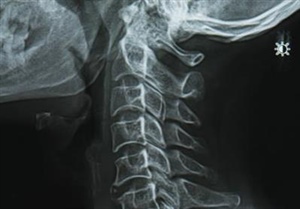

An X-ray was ordered, and there it was: degenerative changes in my cervical spine, most prominent at multiple levels. This wasn’t entirely new territory for me. About six months earlier, when I was experiencing pain in my hip, an X-ray revealed degenerative changes and arthritis there as well. Still, hearing those words—particularly in relation to my spine—gave me pause.

What I’ve come to understand, and what I think is important to share, is that degenerative changes are not a diagnosis of decline; they are a reflection of a life lived. By the time we reach our 60s, most of us have some degree of wear and tear in our joints and spine, whether we feel it or not. The discs in our spine lose some of their cushioning, joints can stiffen, and bone spurs may develop. This is a natural part of aging, not necessarily a signal that something is wrong.